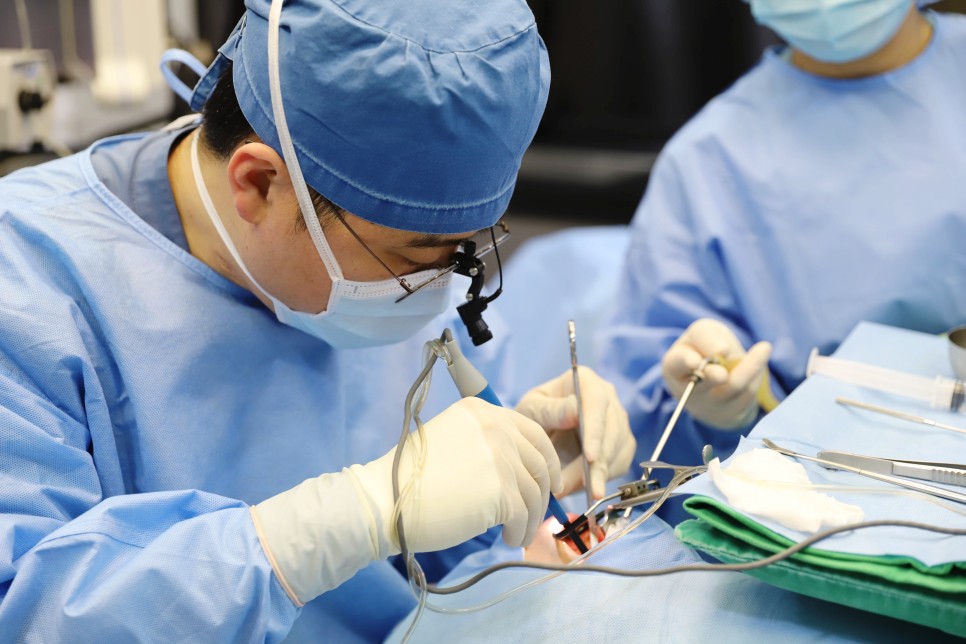

수술은 전신 마취로 이루어졌습니다. 편도전 절제술은 반드시 전신 마취로 수술을 받아야 합니다.

편도를 절제하는 여러 가지 도구가 있습니다. 그 중에서 환자가 선택한 수술 도구는 코브레터였습니다.

코브레이션 기술은 고주파 에너지와 식염수를 결합하여 플라즈마장을 생성하는 기술입니다. 플라즈마 필드는 분자를 분해하거나 세포를 태우지 않고 분자 수준에서 편도선을 정밀하게 절제합니다. 접촉 조직에서 상대적으로 낮은 온도(40~70℃)를 유지하기 때문에 주변 조직의 손상을 최소화할 수 있습니다.

이러한 코브레이션 기술은 고압 에너지를 사용함으로써 주변 조직에 손상을 주고 고통을 초래하는 기존 편도선 절제술의 대안으로 개발되었습니다.

편도 결석이 있는 분은 대부분 만성 편도염을 앓는 경우가 많기 때문에 수술 중 출혈이 많지요. 다행히 오늘 환자는 출혈이 많지 않았어요. 대부분 코브레터 편도 절제술은 출혈이 많지 않으면 양측 절제에 15분에서 30분 정도 걸립니다.

수술 중 출혈이 별로 없으면 수술 후 출혈이 심해질 수 있다는 미신이 있으므로 ^^;;보다 꼼꼼하게 지혈작업을 하여 수술을 마칩니다.AFTER 수술 직후▶▶